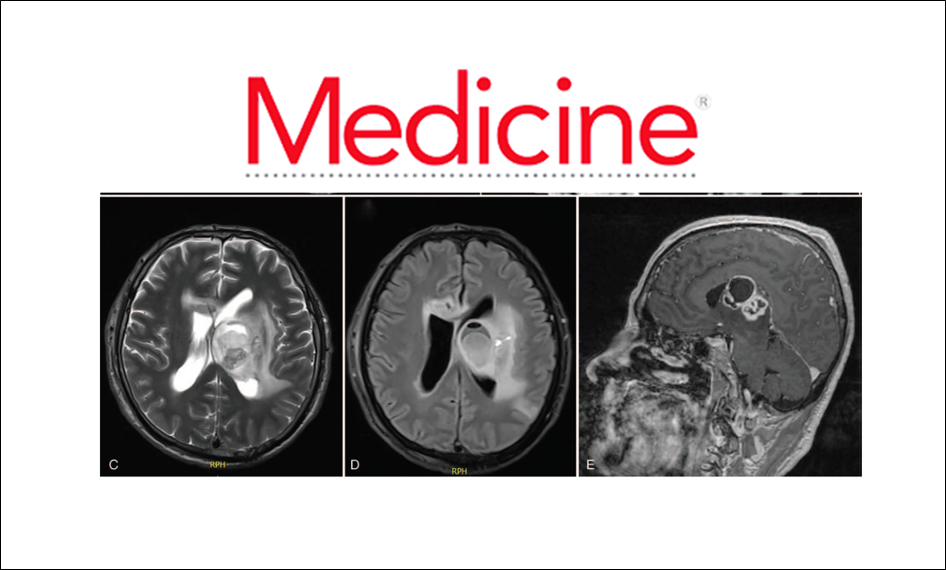

A brain abscess was found and surgically drained. Matrix-assisted laser desorption ionization–time-of-flight mass-spectrometry and heat shock protein 65/16S-23S rRNA gene intergenic spacer genotyping from the sample revealed the etiological agent as Nocardia beijingensis.